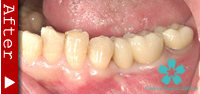

歯を一本だけ失った場合

“失われた1本の歯根の代理品”としてインプラントを1本だけ使って失った歯の部分を修復する方法は、最も洗練された治療方法であり、審美的にも満足のいく結果が得られます。

1本のインプラントによってあたかも自分の天然歯のように自然に感じられます。顎骨の”萎縮”の心配もなく、本来の骨量を維持できます。

ブリッジを入れる時のように、健康な隣の歯を削る必要がありません。